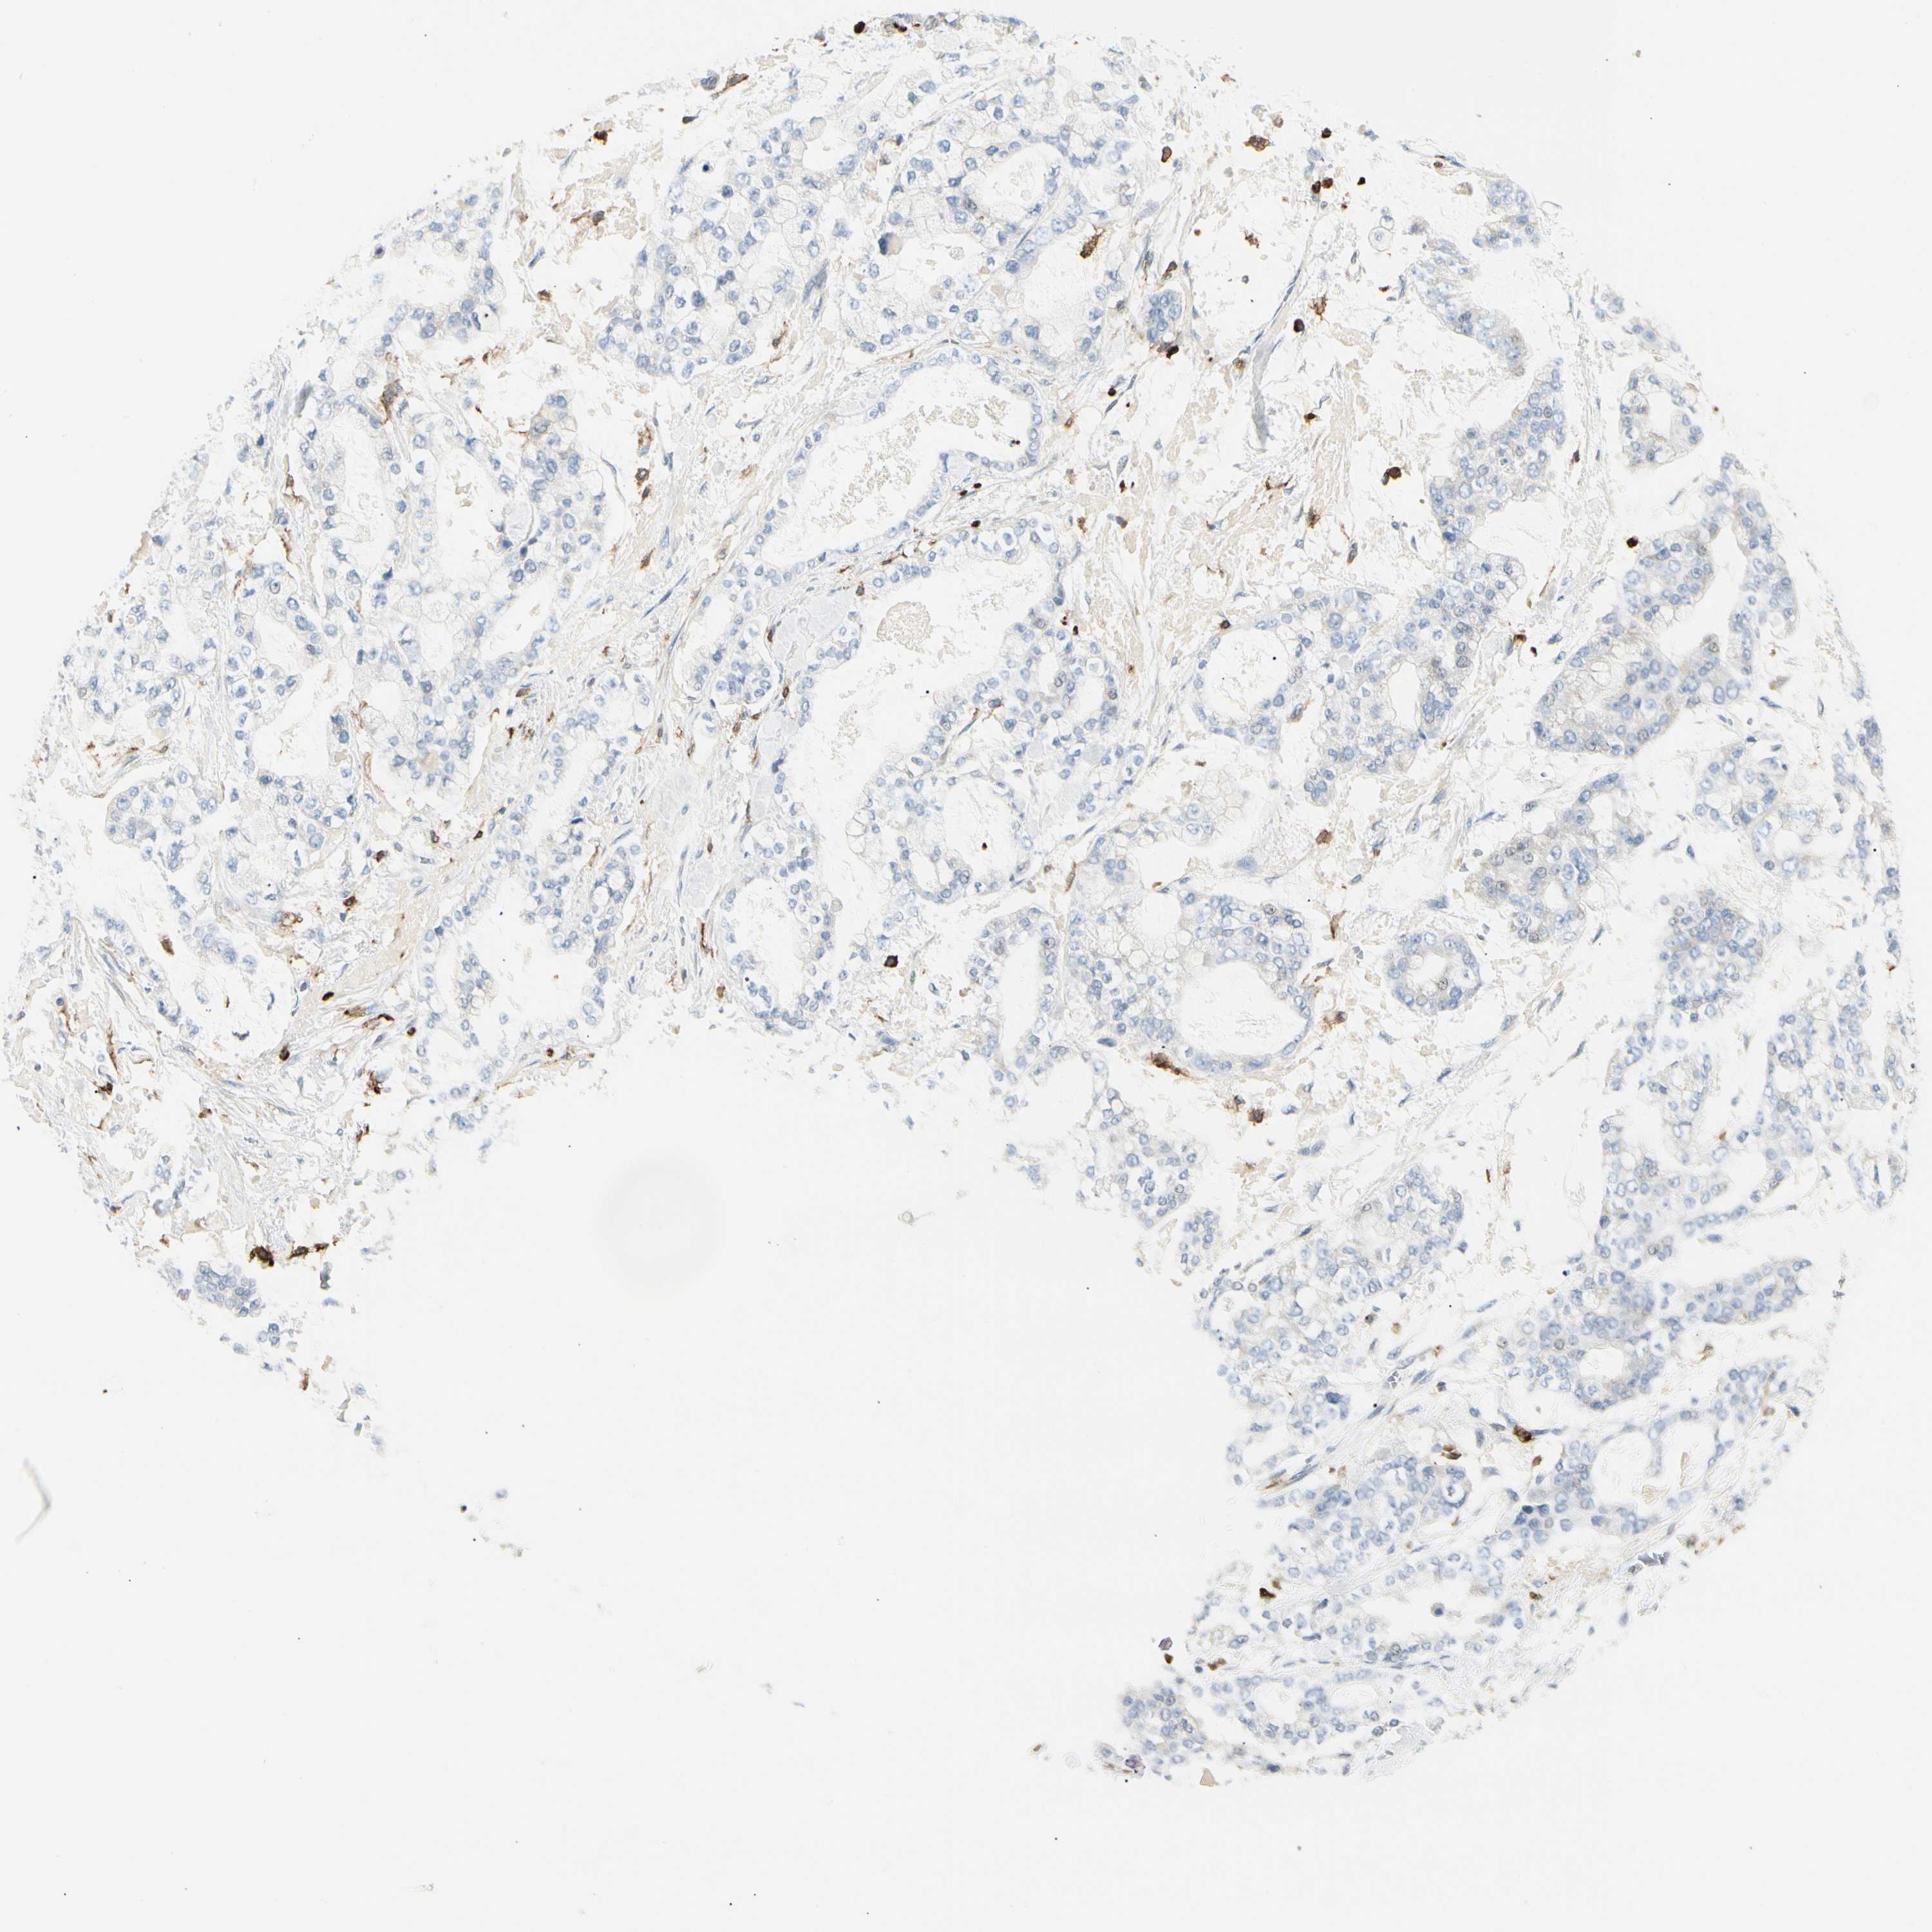

STOMACH CANCER - Protein expressioni

A mouse-over function shows sample information and annotation data. Click on an image to view it in a full screen mode. Samples can be filtered based on level of antibody staining by selecting one or several of the following categories: high, medium, low and not detected. The assay and annotation is described here.

Note that samples used for immunohistochemistry by the Human Protein Atlas do not correspond to samples in the TCGA dataset.

Antibody stainingi

Antibody staining in the annotated cell types in the current human tissue is reported as not detected, low, medium, or high, based on conventional immunohistochemistry profiling in selected tissues. This score is based on the combination of the staining intensity and fraction of stained cells.

Each image is clickable and will lead to virtual microscopy that enables deeper exploration of all samples and also displays staining intensity scores, fraction scores and subcellular localization as well as patient and tissue information for each sample.

Antibody HPA016894

Adenocarcinoma, NOS